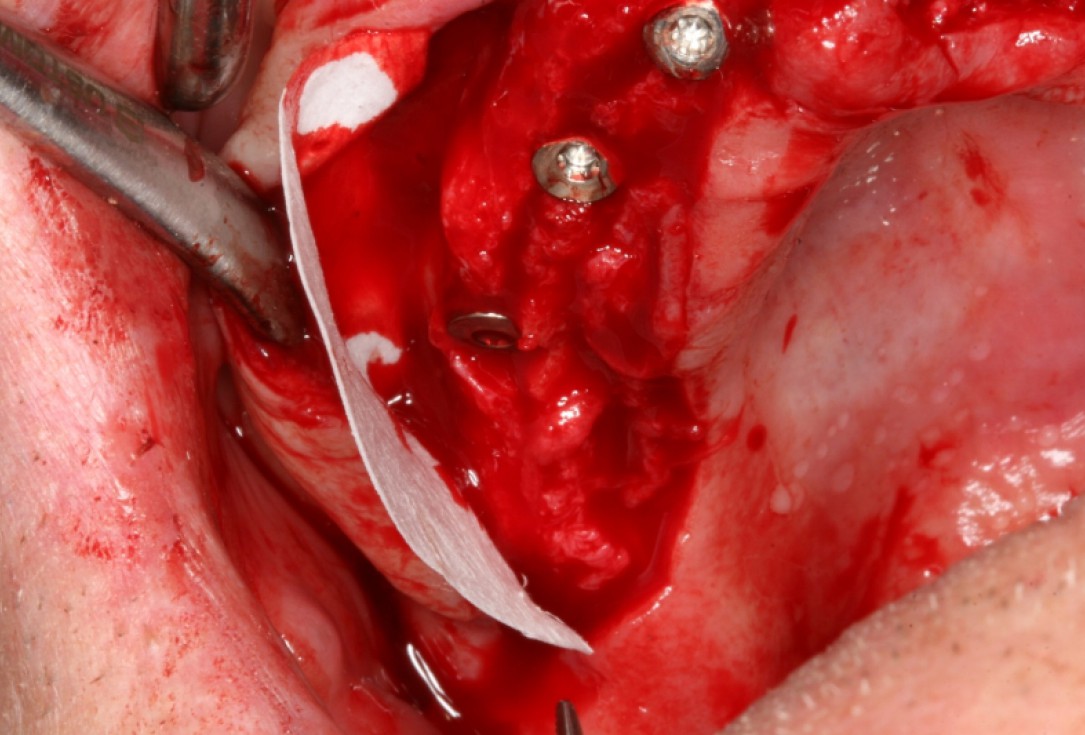

03/10 - Positioning of collprotect® membrane for application of bone graft materialCircular bone splitting with maxresorb® & collprotect® membrane - PD Dr. J. Neugebauer